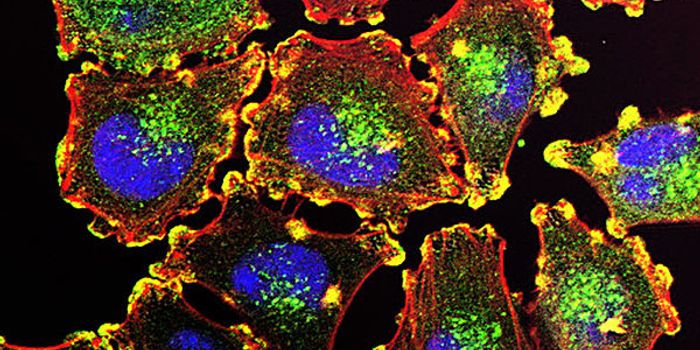

APR 28, 2022CancerIt is estimated that over 250.000 men in the United States will receive prostate cancer diagnoses in 2022, acc ...